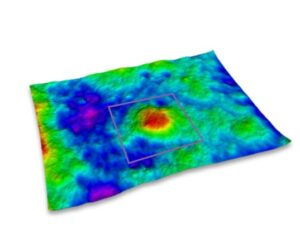

You can also perform 3D acquisitions of the skin surface. Thanks to a technique called stereo photometric, the C-Cube analyses several images under different lighting conditions. The software estimates surface normals. Combined with geometric calibration, it produces elevation information at every pixel.

Thanks to its unique ability to measure 3D parameters, it is possible to measure button elevation in terms of peak height (Sp) and total amplitude (Sz), proving that the product under test has an effect if the peak elevation decreases over time.

Pimple elevation Peak height and amplitude